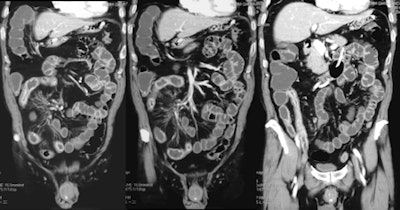

Small-bowel CT enteroclysis. Crohn's disease extended throughout the ileum, with thickened wall and typical enhancement of the mucosal layer. Fibrofatty proliferation of the mesentery, also known as creeping fat, is visible. Image courtesy of Dr. Gian Rollandi of Ospedali Galliera in Genoa, Italy.CT has a high sensitivity and specificity for detecting luminal and extraluminal disease and complications, and yields images with high temporal and spatial resolution with a short acquisition time compared with conventional enterography and MRI. However, a standard CT of the abdomen and pelvis (CTAP) exposes the patient to a radiation dose of about 8 mSv (literature range 3.5-25 mSv). The radiation exposure from CTAP is substantial compared with chest radiography (0.02 mSv), plain film of the abdomen (0.7 mSv), and barium studies (3.5-5 mSv), O'Neill explained in a presentation at the RSNA 2011 meeting in Chicago.

Typical indications for CT in Crohn's disease include establishing the initial diagnosis and quantification of disease distribution, extent, and activity, as well as assessment for complications such as active enterocolitis, abscess, fistula, stricture, and lymphadenopathy.